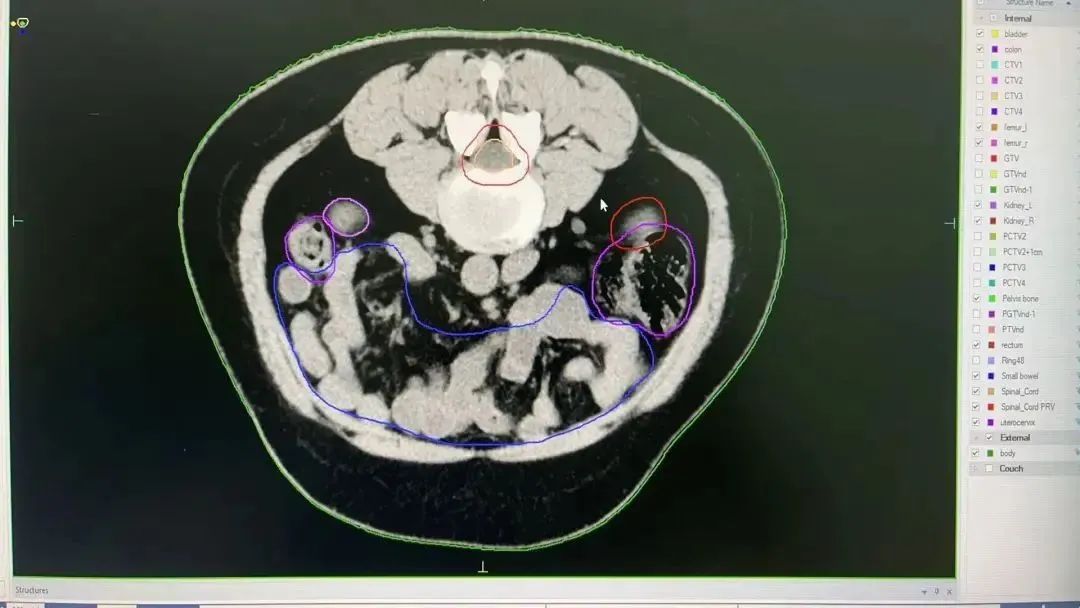

在肿瘤放疗科,直线加速器搭载AI自动勾画系统,精准定位肿瘤靶区与危及器官,有效保护正常器官,帮助医生快速、准确地确定放疗范围,显著提高放疗计划的精准性,为肿瘤患者提供更优质、更有效的治疗方案。